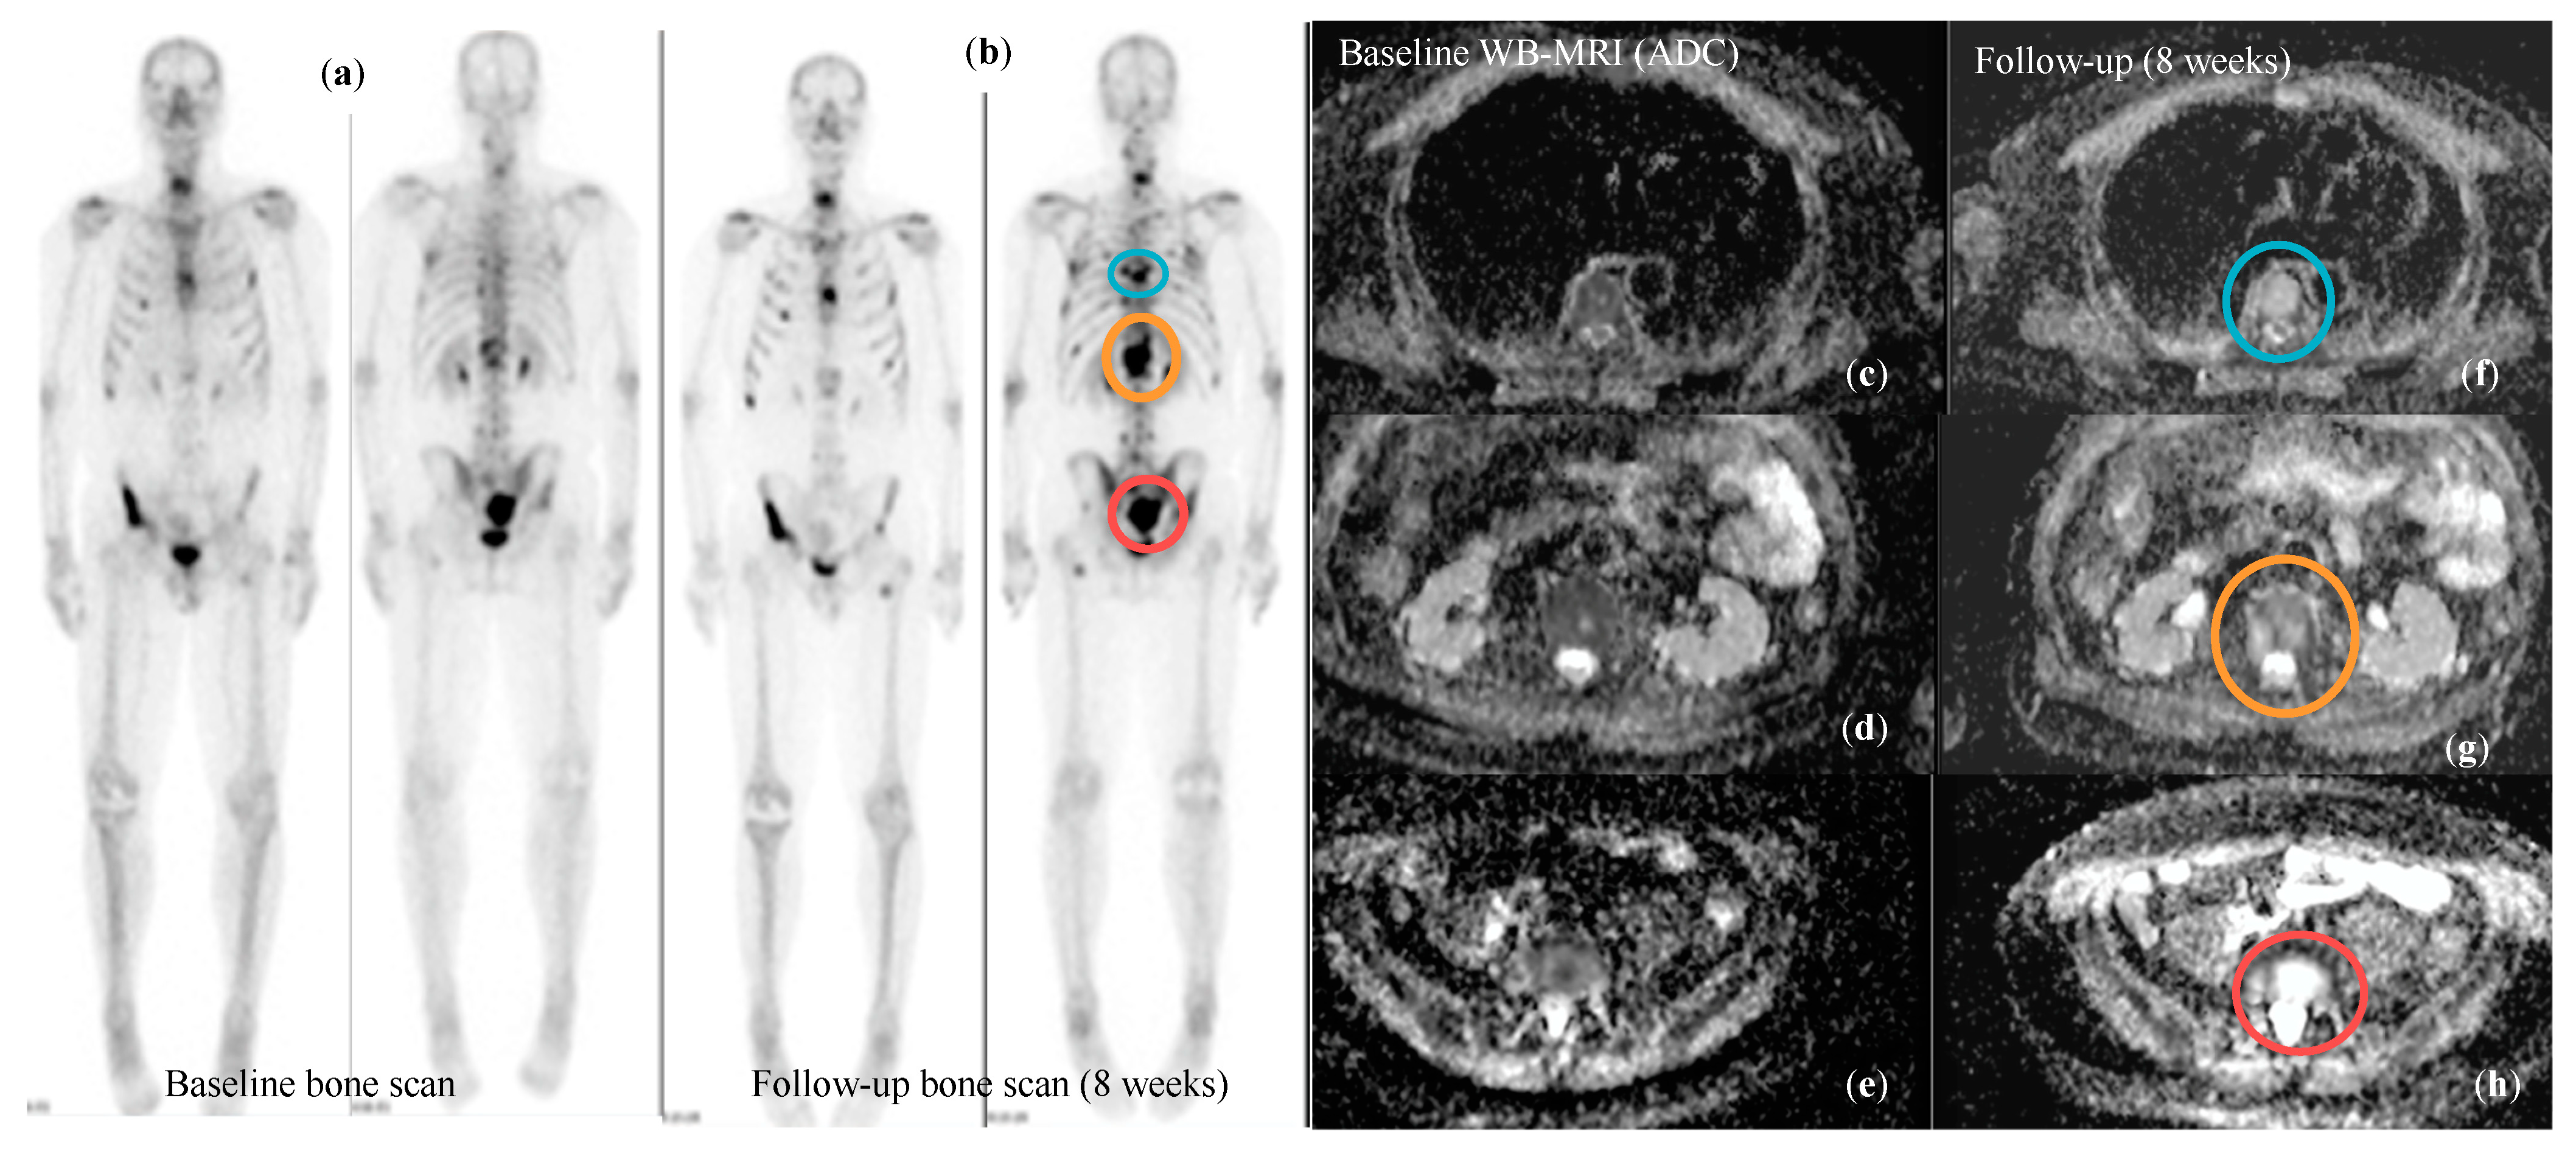

3.5. Response Assessment in Metastatic Prostate Cancer

| Messiou et al. Eur Radiol 2011 [102] | Diffusion Weighted MRI | Overall ADC of bone lesions increases both in responders and progressors, but the magnitude of increase if higher for responders. An increase in overall ADC > 25% is 75% sensitive and 66.6% specific for response. ADC alone cannot confidently assess response or progression as the changes in bone marrow composition significantly influence ADC values. | |

- Perez-Lopez, R.; Mateo, J.; Mossop, H.; Blackledge, M.D.; Collins, D.J.; Rata, M.; Morgan, V.A.; Macdonald, A.; Sandhu, S.; Lorente, D.; et al. Diffusion-weighted Imaging as a Treatment Response Biomarker for Evaluating Bone Metastases in Prostate Cancer: A Pilot Study. Radiology 2017, 283, 168–177. [Google Scholar] [CrossRef]

- Blackledge, M.D.; Collins, D.J.; Tunariu, N.; Orton, M.R.; Padhani, A.R.; Leach, M.O.; Koh, D.-M. Assessment of treatment response by total tumor volume and global apparent diffusion coefficient using diffusion-weighted MRI in patients with metastatic bone disease: A feasibility study. PLoS ONE 2014, 9, e91779. [Google Scholar] [CrossRef]